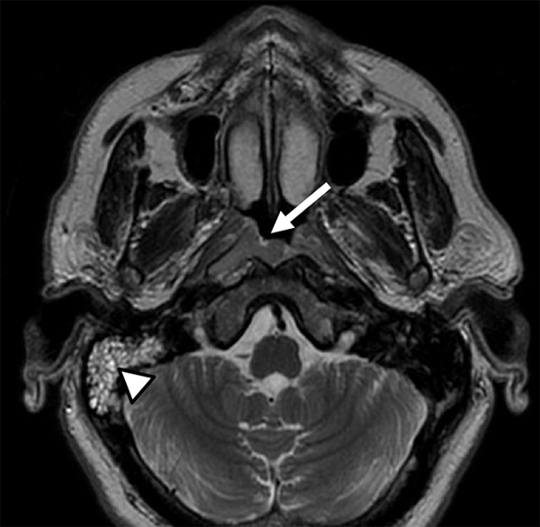

Preparado anatómico de una hemicara izquierda donde se muestra al segmento extracraneal del nervio facial (flecha), cruzando a la arteria temporal superficial (cabeza de flecha).

Corte axial de RM en imágenes ponderadas en T1 post- contraste. Paciente que consultó por caída de la comisura labial izquierda e hipoacusia derecha. Se identificó refuerzo post-contraste de los segmentos del nervio facial canalicular, laberíntico, ganglio geniculado y timpánico izquierdos, patognomónicos de la parálisis facial idiopática (o parálisis de Bell). En el conducto auditivo interno derecho, se observó una lesión focal redondeada hiperintensa compatible con schwannoma del nervio vestibular, principal diagnóstico diferencial de la parálisis de Bell.